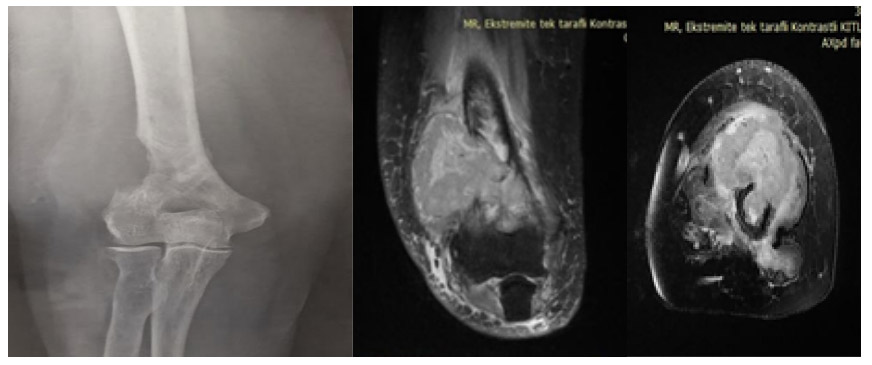

Before surgery: X-ray shows bone destruction in the lower outer portion of the right humerus, and MRI reveals a large tumor mass extending beyond the bone.